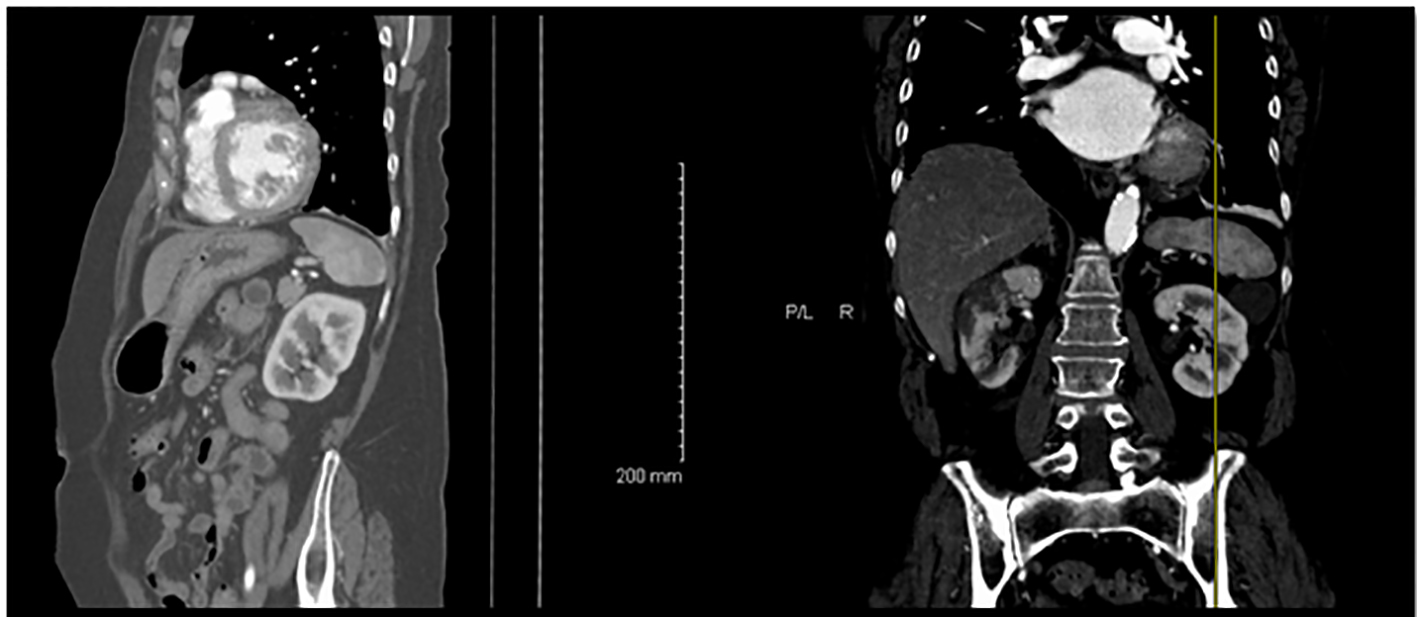

She had a non-contrast abdominal computed tomography (CT) scan that showed right-sided kidney infarct with small left-sided kidney infarcts (Fig. 1). A CT angiogram of the chest and abdomen revealed no aortic pathology but did confirm bilateral kidney infarcts. She had a transthoracic echo that showed moderate left atrial enlargement with no clot and normal left ventricular ejection fraction.

![]() Click for large image | Figure 1. CT scan of the abdomen showing bilateral kidney infarctions. |